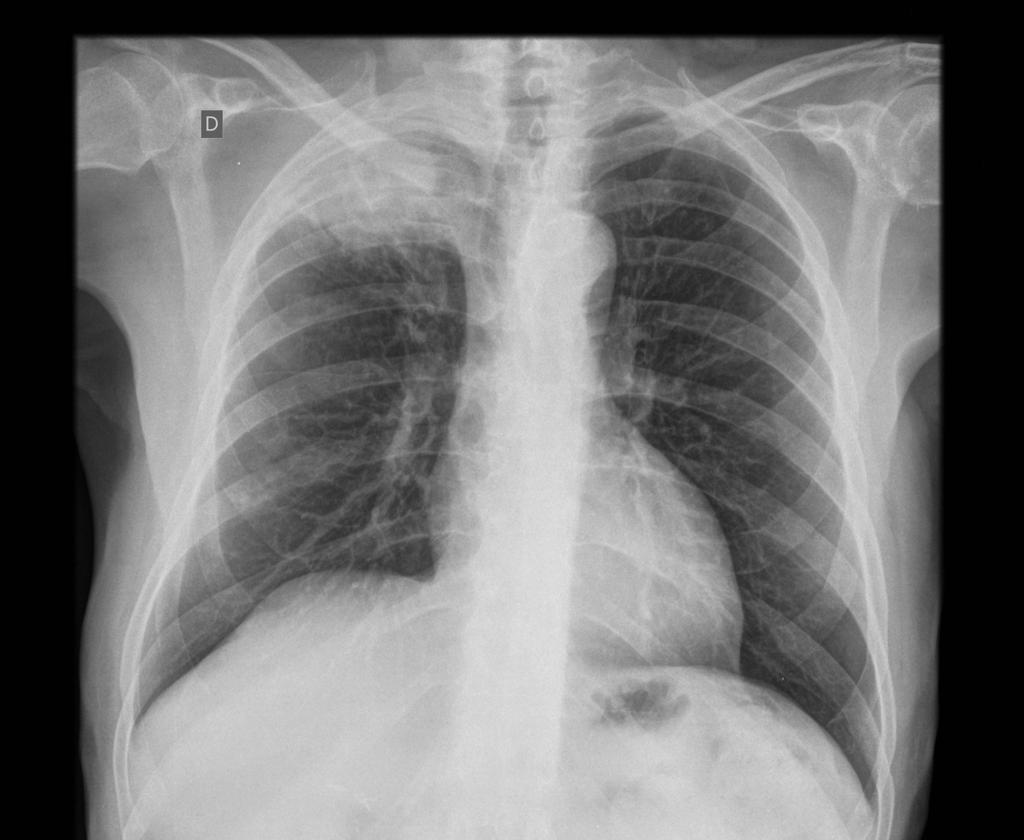

What are the three stages of congestive cardiac failure?